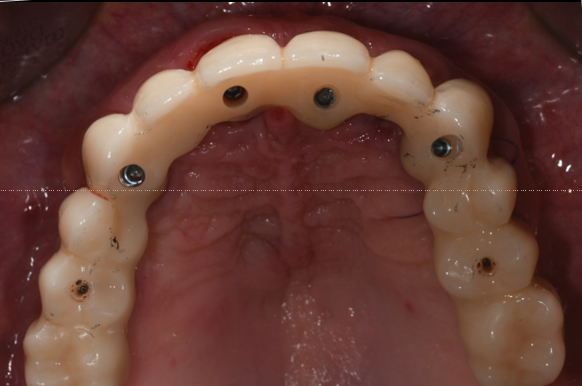

The photogrammetric dataset was transferred to the dental laboratory, enabling same-day fabrication of a milled long-term provisional. The provisional restoration was seated on the afternoon of surgery, restoring aesthetics and function immediately.

Healing Phase and Prosthetic Release

Healing progressed without complications. Stable peri-implant soft tissues and successful osseointegration were observed. After removal of the provisional restoration, a second intraoral photogrammetry scan was performed to document the implant positions at the time of prosthetic release. These data were transferred to the patient’s general dentist for final restoration fabrication.